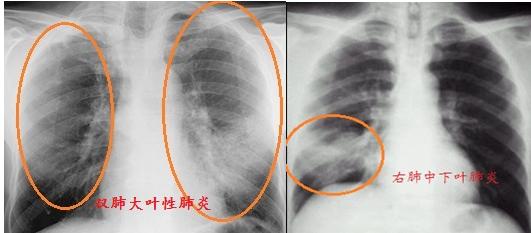

肺炎常见大叶性肺炎和支气管肺炎。大叶性肺炎起病急,胸片可见肺部纹理增粗,联结呈斑片状,位置不定。重度患者可见大片状阴影,甚至全肺布满阴影,肉眼见胸片中全肺变白。当感染得到控制,肺部阴影密度将逐渐降低,片状阴影逐步消散至条索状,直至吸收。

支气管肺炎多见于儿童、老年人及体质低下患者,常见支气管周围肺纹理增强、模糊,多延气管走向分布,严重者条索状影可融合成斑片、大片状阴影。